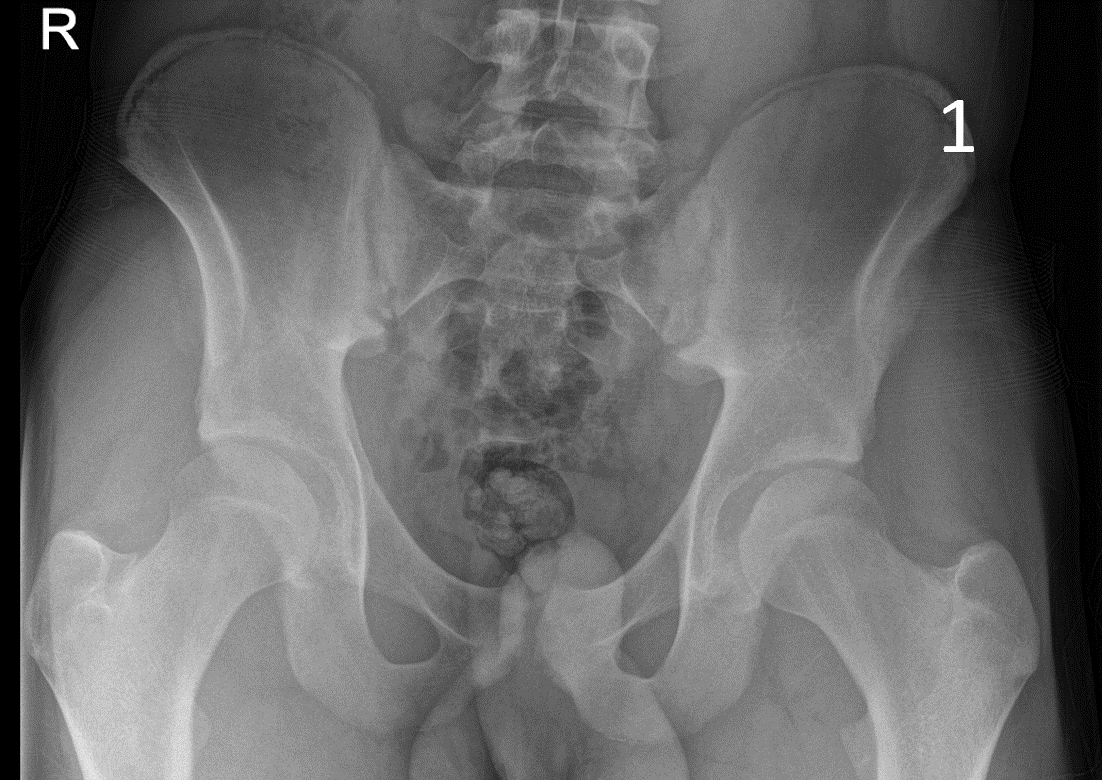

A 17-year-old male presented with severe pain in his right groin. He felt a ‘pop’ in his right groin whilst sprinting and was struggling to weight-bear. A radiograph excluded any bony abnormality (Figure 1) and an ultrasound scan showed no evidence of inguinal or femoral hernia.

The patient was focally tender in the right iliac fossa at the level of the anterior superior iliac spine (ASIS). At this site, there was muscle fibre disruption and a haematoma at the insertion of the sartorius tendon with minimal retraction (Figure 2). There was cortical irregularity at the ASIS and a bony fragment within the retracted tendon and also neovascularisation here on power Doppler (Figure 3). On comparison to the contralateral side, there was altered architecture of the sartorius muscle with a clear defect while the left side looked normal (Image 4). Ultrasound appearances in keeping with a sartorius tendon avulsion. This was treated conservatively with rest, analgesia and a return to normal activities after two months. Surgical interventions are uncommon and are reserved for when the fracture fragment has migrated more than 3cm.

This injury is associated with young athletes plus young rugby and football players.